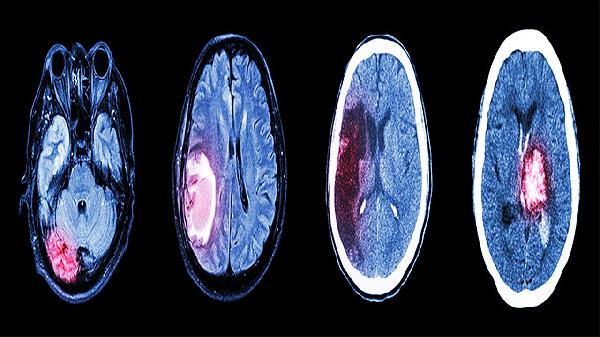

严重颅脑损伤能恢复正常吗

严重颅脑损伤能否恢复正常需根据损伤程度和个体差异综合判断,部分患者通过规范治疗可显著改善功能,但可能遗留不同程度后遗症。 损伤范围局限且未累及关键脑区的患者,早期接受手术清除血肿、降低颅内压等措施后